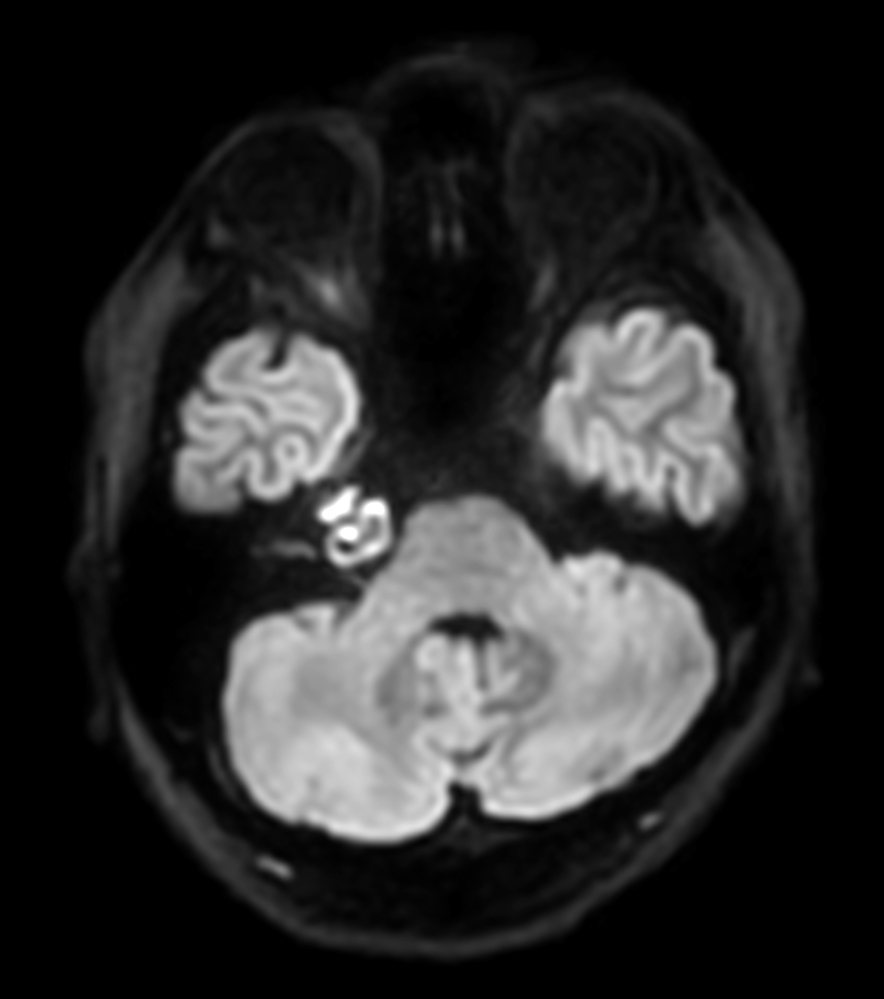

Patient with an IAC lesion. Comparing different DWI methods (EPI, TSE, ZOOM). Compressed SENSE is added to all TSE sequences to decrease scan times, thereby shortening the time the patient has to spent in the magnet. The dS Head 32ch coil is used to enhance image quality.

DWI TSE XD (b1000)

DWI TSE XD high res (b1000)